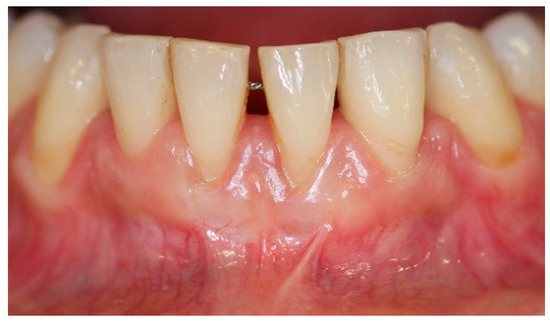

5. Materials and Methods

6. Results